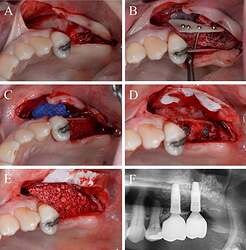

Fig. 3.

Alveolar ridge augmentation of the posterior maxilla. A Initial intraoperative situation with an extended alveolar defect of the posterior alveolar jaw. B Intraoperative situation after sinus floor elevation and fixation of two allogeneic cortical bone plates buccal and palatinal using four fixation screws. C Intraoperative situation after filling sinus floor with xenogeneic bone substitute, covering it with PTFE matrix and filling the alveolar crest with allogeneic spongious granules. D After 4 months, sufficient bone remodeling, screws removed, and implants inserted. E Overlining with xenogeneic granules for resorption protection and covered by collagen matrix. F X-ray demonstrating inserted implants.